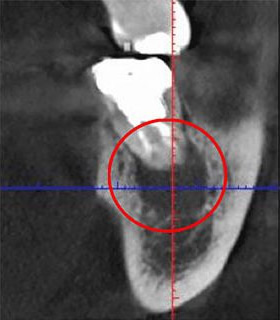

黒い部分が「根管」です。狭く、複雑な形状をしています。

細かい神経や血管が詰まった根管内をきれいにするのが「根管治療」ですが、その繊細さを極める治療を、いまだに多くの歯科医院が肉眼で行っています。当医院では「高倍率ルーペ」や「CT」といった精密機器を用いて、肉眼では捉えきれない箇所までを見える(可視化)状態にしてから治療を行います。

画像が鮮明になることで、治療の精度も大きく変わります。次の写真は、同じ部位を「CT」(左)と「レントゲン」(右)で撮影した画像です。黒い影は問題が発生している箇所で、左の「CT画像」にはしっかり映っていますが、右の「レントゲン画像」にはありません。

レントゲンだけで撮影をしていたら、この問題は見落とされていたことでしょう。そのまま治療が行われなければ、炎症が悪化して、最終的に「抜歯」になっていたかもしれません。CTで撮影していれば、見落とされること無く、適切な治療が行えます。